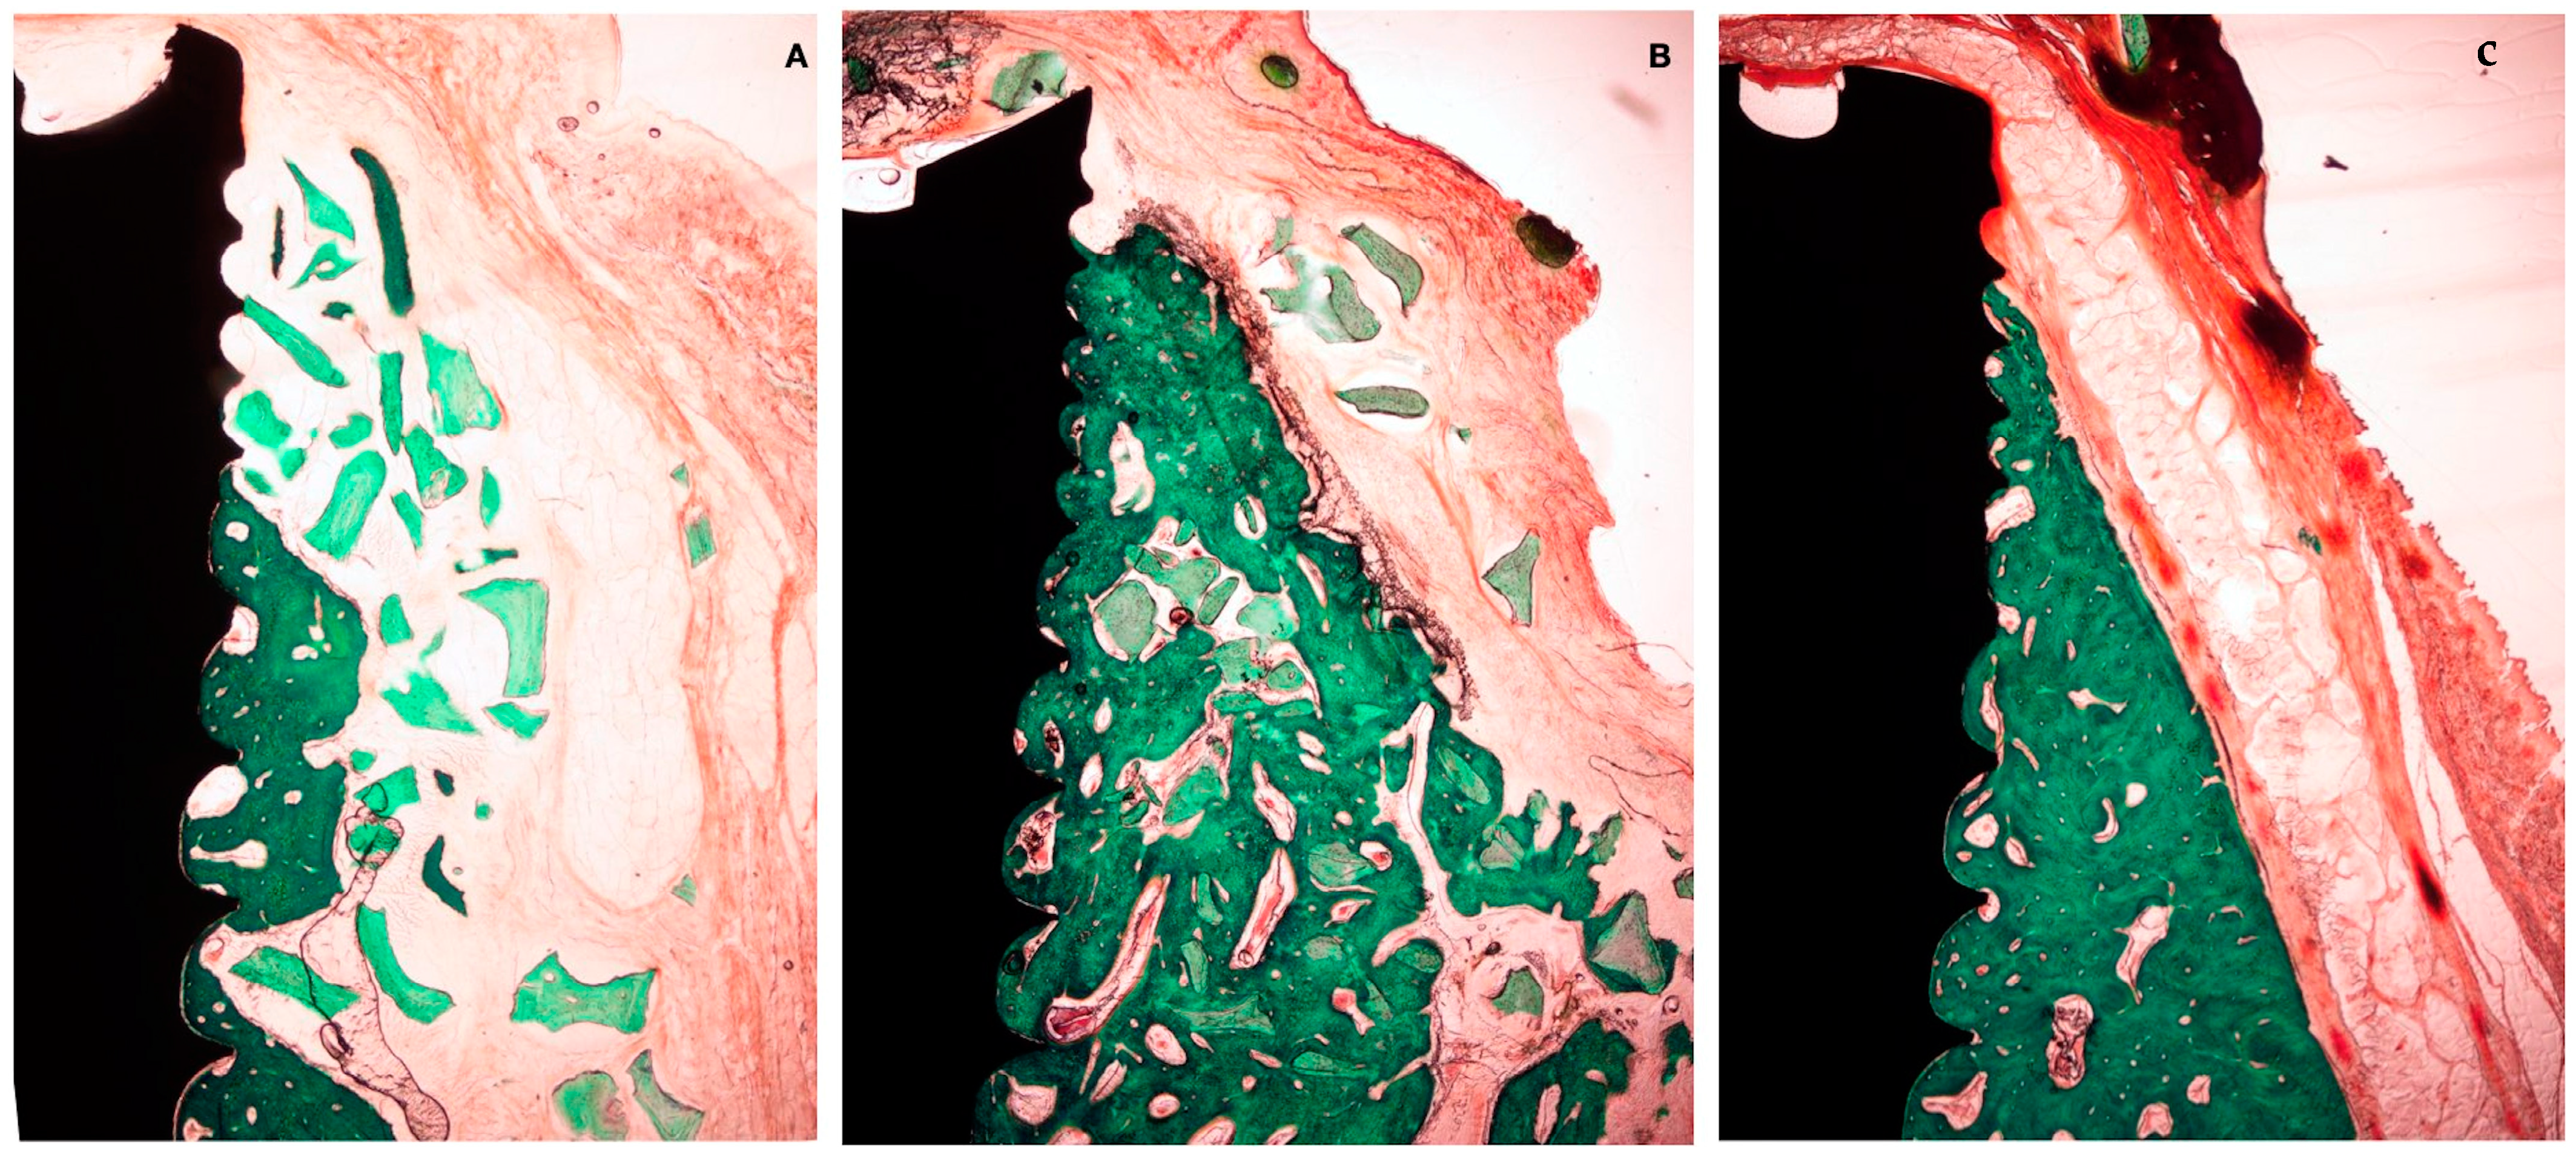

3.1. Histological Observations

3.2. Histo-Morphometric Measurements